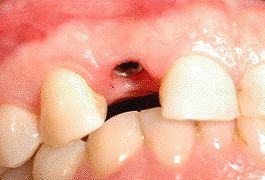

L'uso di impianti in "zirconio" rappresenta una soluzione molto interessante per l'estetica dei denti anteriori. Attualmente solo la parte esterna, quella visibile, viene proposta in zirconio bianco mentre la parte inserita nell'osso è sempre costituita da titanio, materiale che vanta decenni di esperienza e viene abitualmente impiegato in ortopedia. Ovviamente, durante la visita specialistica, devono essere valutati i presupposti necessari per un impianto a carico immediato, quali ad esempio l'assenza di infezione nella zona da trattare e la presenza di una buona densità ossea che consenta stabilità primaria alla "radice artificiale" ossia all'impianto. Diventa quindi fondamentale una visita da parte dell'implantologo, per discutere dei propri desideri e valutare la situazione clinica individuale.

Non sempre ogni dente necessita di un proprio impianto, ad esempio nella figura accanto possiamo vedere quattro denti sostenuti da tre soli impianti.